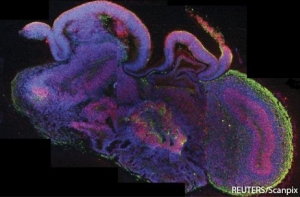

Образцы достигают всего несколько миллиметров в длину и образованы из многочисленных слоев клеток серого вещества, строение которых приближено к настоящим отделам мозга, развивающегося у эмбриона. Исследования позволят ученым проанализировать факторы, влияющие на возникновение таких психических заболеваний, как шизофрения и аутизм.

«Полученные «органоиды» показывают отдельные регионы центрального отдела нервной системы человека на его ранних стадиях развития. Это также включает в себя и формирование легко различимой коры головного мозга, которая является самой значительной его частью», – передает ИТАР-ТАСС слова одного из авторов исследования Мэдлин Ланкастер.